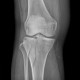

ALO Dokter,Dok, saya dapat pasien wanita (51 tahun) yang tertabrak mobil saat berdiri di trotoar. Apa diagnosis yang tepat pada kasus fraktur ini serta tata...